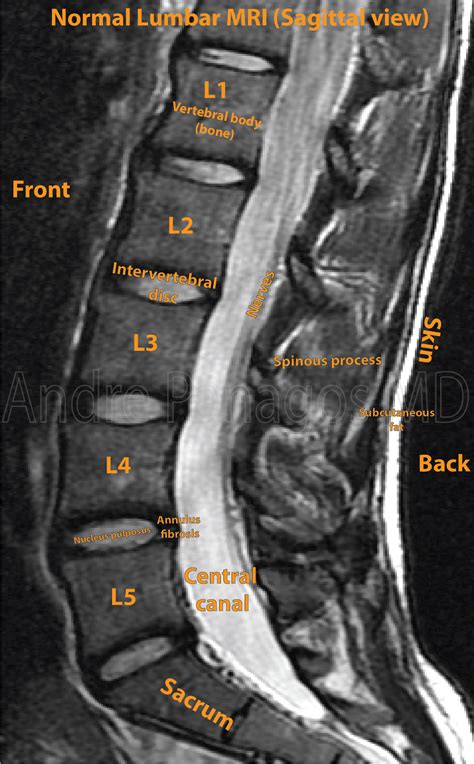

How To Read A Mri Scan. Mri is the most frequently used imaging test of the brain and spinal cord. Conversely, the cerebrospinal fluid (csf) is bright in t2 due to its’ water content.

T2 is generally the more commonly used, but t1 can be used as. Mri of the brain and spinal cord. Brain mri examination should follow a systematic approach starting from the midline and going laterally. Typically, the radiologist sends the report to the person who ordered your test, who then delivers the results to you. Web in this tutorial, you will learn the basic knowledge required for interpretation of mri scans. To support the facts within our articles. They'll then issue a radiology report within a few days, which your healthcare provider will review with you. The tutorial covers the basic physics necessary to understand how mri images are formed. Web how to read brain mri. The radiologist writes the report for your provider who ordered the exam.

Many patients can now access their electronic health records online. Typically, the radiologist sends the report to the person who ordered your test, who then delivers the results to you. Web mri with contrast scans are interpreted by a radiologist who will review the findings in context with previous scans and your available medical history. Thus, the brain mri analysis shall start from the ventricles, going to the surrounding subcortical structures, brain lobes, cerebral cortex, to the meninges and skull. You will learn about the different types of mri images commonly encountered and a systematic approach to image interpretation. Brain mri examination should follow a systematic approach starting from the midline and going laterally. The radiologist writes the report for your provider who ordered the exam. Mri is the most frequently used imaging test of the brain and spinal cord. The glenohumeral joint is a synovial joint, formed by the glenoid fossa of the scapula and the head of the humerus, while the. It's often performed to help diagnose: The tutorial covers the basic physics necessary to understand how mri images are formed.